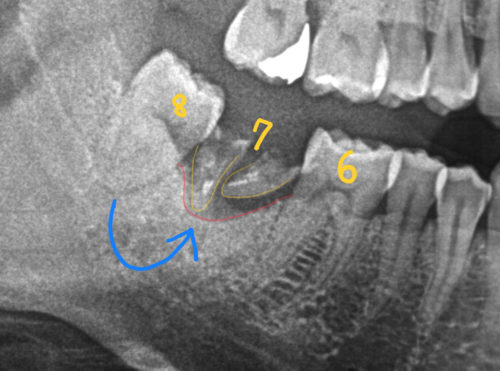

この方の『7』の歯のように、保存が難しい場合、抜いた後に欠損を補う方法として、

親知らずの移植、という処置があります